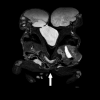

BACKGROUND Conjoined twins are a rare congenital anomaly with various types, depending on the connection site. Managing these cases requires a structured approach leading to separation surgery. This report provides a detailed description of the anesthetic strategies and challenges of pygopagous conjoined female twins who underwent 2 surgeries before separation at 17 weeks of age. CASE REPORT The female twins were conjoined at the sacral level (S4), with fused thecal sacs at L5 and cord tethering, with the conus terminating below L3 in both patients. They had separate rectal ampullae that fused into a single anal canal in the midline in a Y formation. The babies underwent 2 surgeries prior to separation: meningocele repair for twin B and anal canal dilation and sphincter mapping for both twins, followed by a ventriculoperitoneal shunt insertion for twin B. The separation surgery included dividing the bony vertebral fusions and dural sacs, untethering the spinal cords and nerves, and correctly allocating the intrapelvic muscles, guided by sphincter muscle mapping. Anesthesia was managed by 2 distinct teams each time, with duplicated equipment and color-coded medications to prevent errors. Due to the critical condition of twin B, general anesthesia was administered to her first. The report also addresses the challenges faced during the 3 surgical procedures. CONCLUSIONS Anesthetic management for pygopagus twins presents complex challenges. Despite limited experience with similar cases, successful management was achieved through planning, effective communication, and rehearsal of unfamiliar setups. Attention to detail and involvement of highly experienced teams were crucial to the success of the procedures.